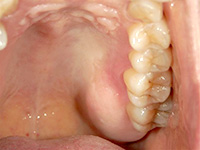

結合組織移植術

他の箇所とかわりなく、きれいな歯ぐきになりました。

上顎裏側の結合組織を摘出しています。術後の傷も、きれいに治りました。